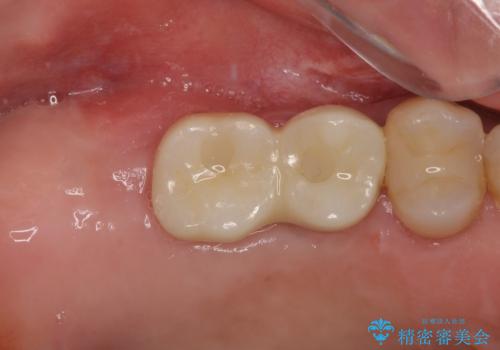

ラミネートベニアは切削量が少ないことがメリットとしてあげられますが、色調を周辺と合わせられないこと、接着境界線が長く汚れや歯石が溜まりやすいことがデメリットとして考えられます。

また、接着境界線にむし歯がある場合には適用外となるなど、適用症例を選ぶため、治療に際して担当医としっかりと相談することが大切です。